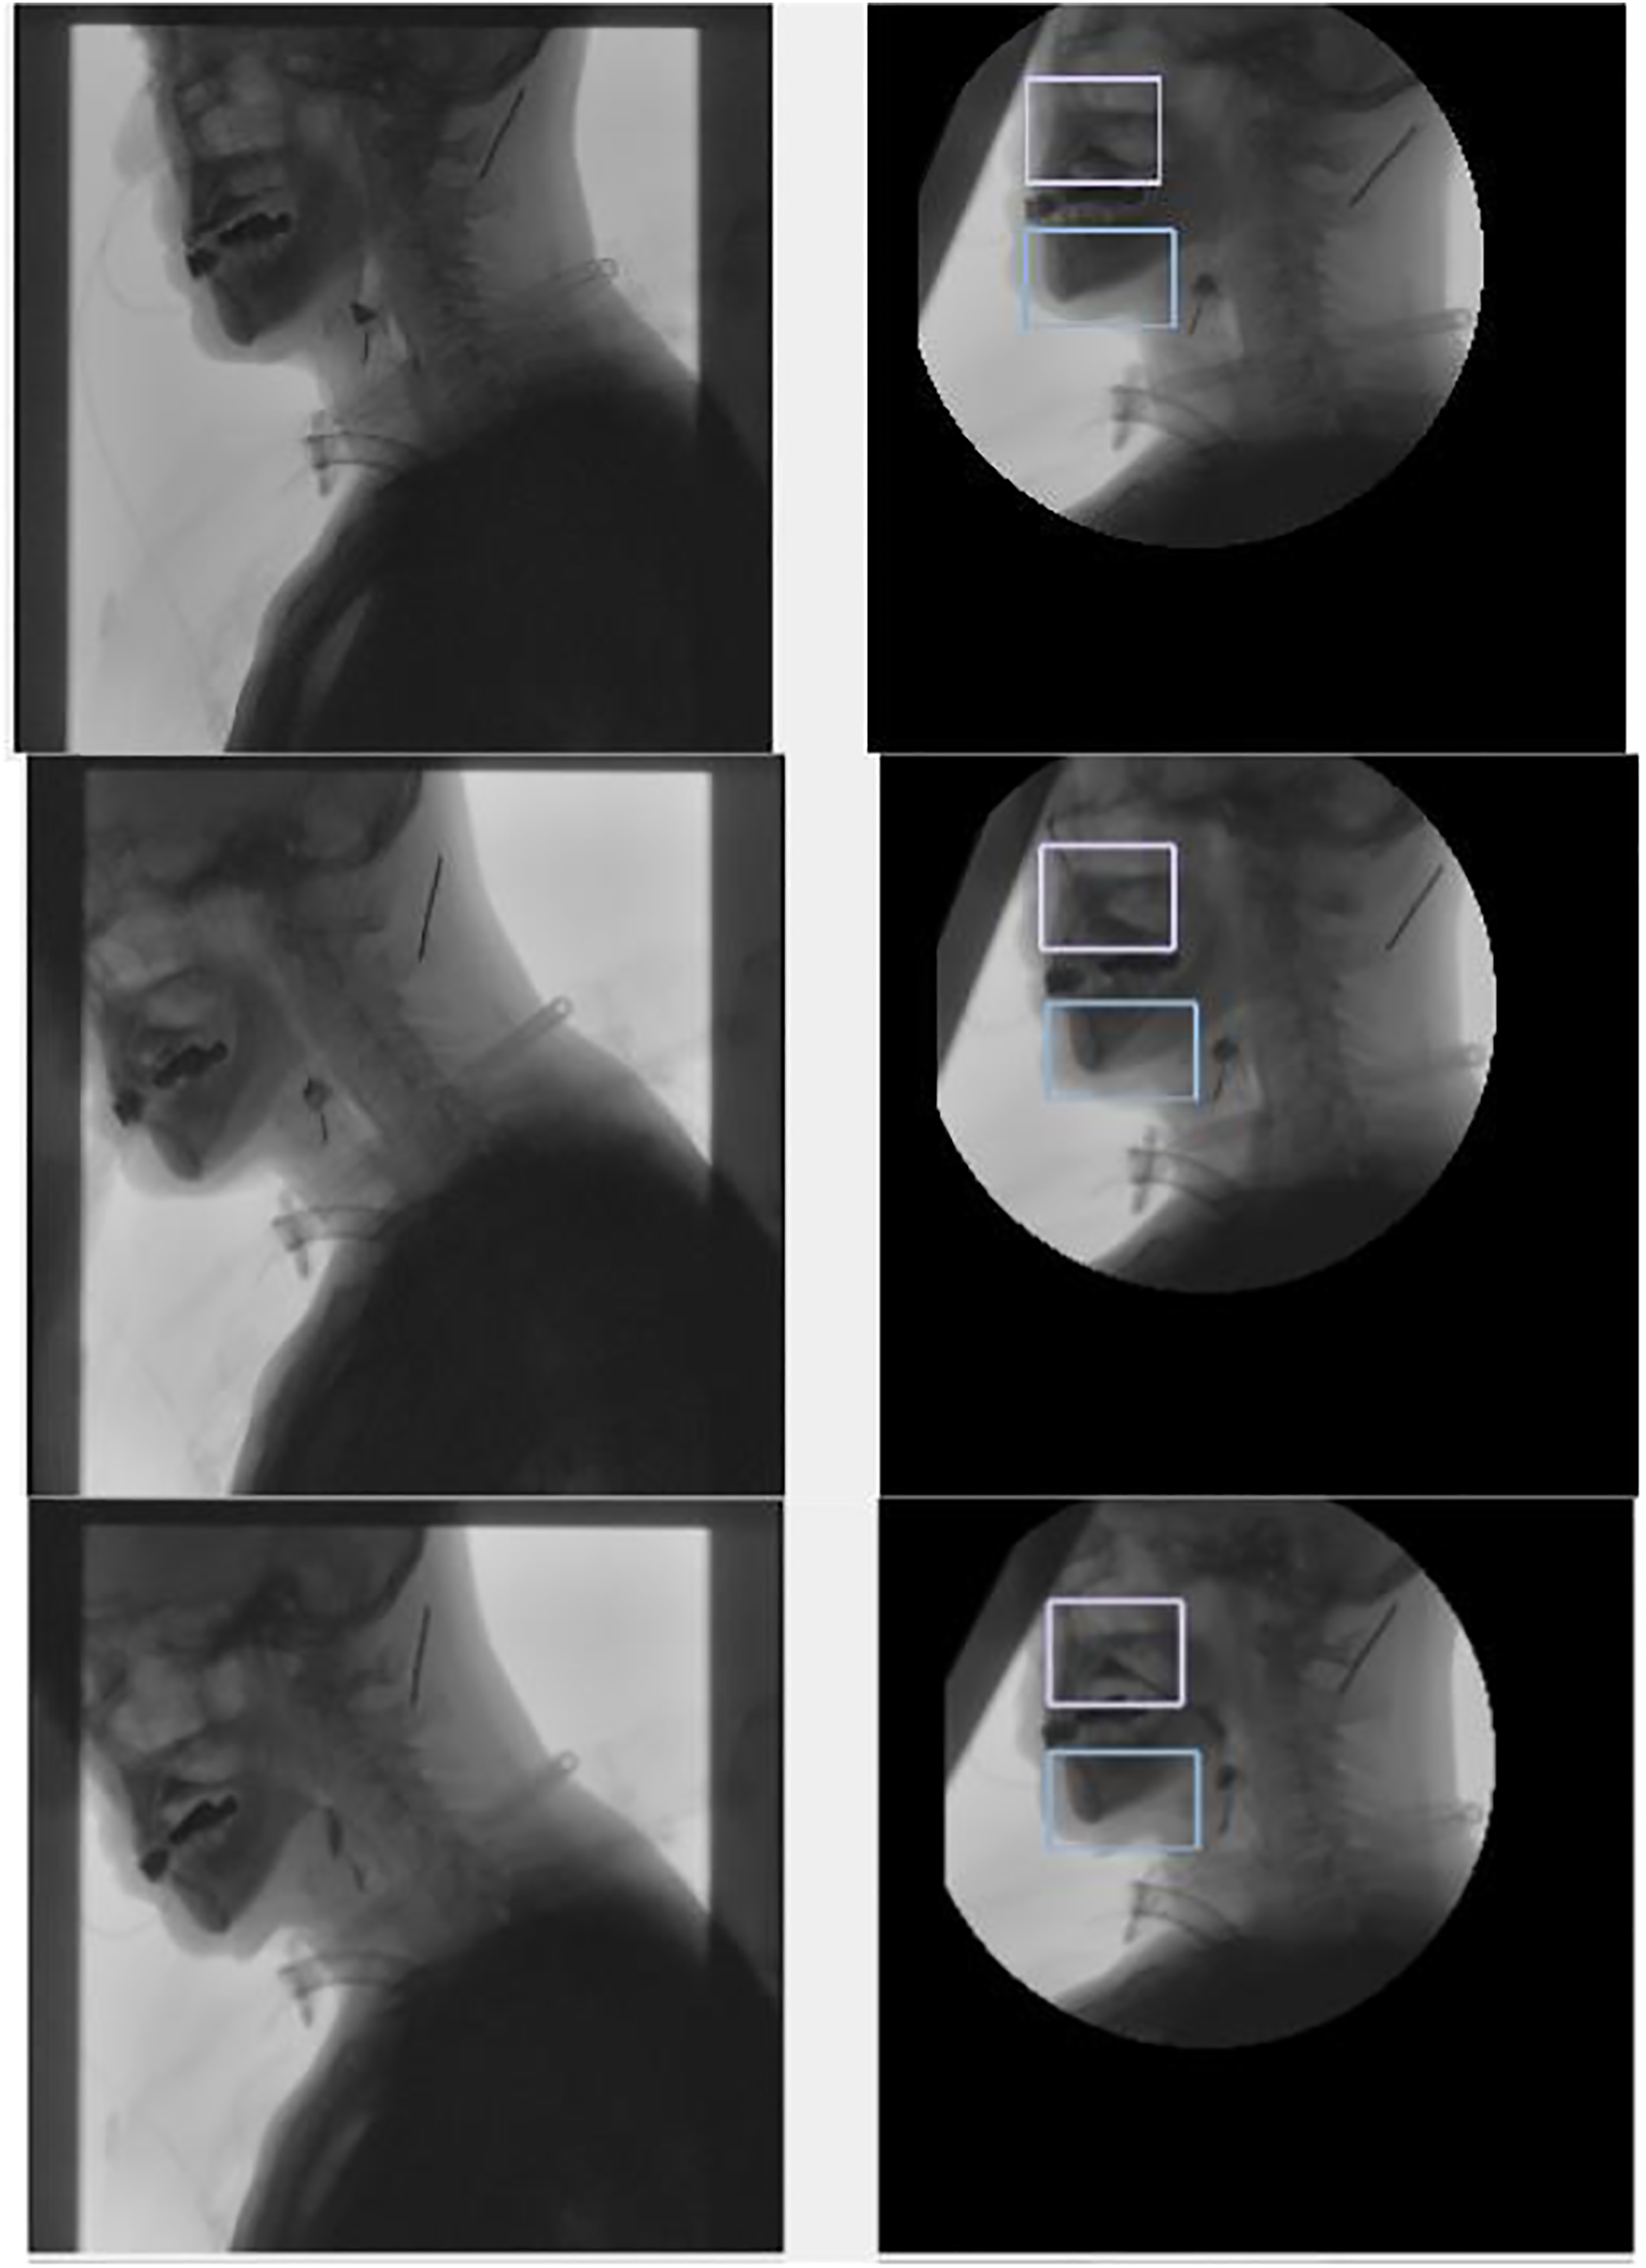

According to the tracking results (Figures 11, 12), the tracking effect after rotation is more intuitive, and it is more convenient to calculate the position relationship between tissues and organs.

FIGURE 12. Tracking the chin and nasal cavity. The left one is the original image, and the right one is the tracking results in the coordinate system of the spine.